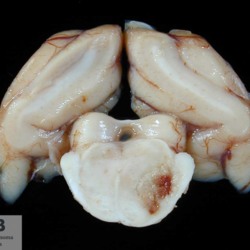

Pàgina anterior de 637 Pàgina següent 3181 total Ovine Specie: Ovine Organ: Lung Lesion: Bronchitis Lesion modifier: Bronchitis - Catarrhal Disease: Oestrosis Position: 253 (1 views) Equine Specie: Equine Organ: Ovary Lesion: Teratoma Lesion modifier: - Disease: - Not viewed Feline Specie: Feline Organ: Brain Lesion: Meningoencephalitis Lesion modifier: Meningoencephalitis - Necrotizing Disease: Toxoplasmosis Files/Expedient: N-297/07 Position: 253 (1 views) Feline Specie: Feline Organ: Brain Lesion: Encephalitis Lesion modifier: Encephalitis - Granulomatous Disease: Toxoplasmosis Files/Expedient: N-297/07 Not viewed Feline Specie: Feline Organ: Lung Lesion: Pneumonia Lesion modifier: Pneumonia - Interstitial Disease: Toxoplasmosis Files/Expedient: N-31/16 Position: 253 (1 views) Pàgina anterior de 637 Pàgina següent Títol Select...Avian (Exotic) (110)Avian (Poultry) (76)Bovine (317)Canine (935)Caprine (47)Equine (257)Feline (326)Ferret (19)General (127)Marine mammal (22)Non-human primate (20)Ovine (328)Porcine (379)Rabbit (61)Reptile (38)Rodent (28)Wildlife (91) Format Select...- (60)Abomasum (37)Adrenal gland (10)Blood (7)Blood vessel (50)Body as a whole (19)Bone (57)Bone marrow (21)Brain (93)Cloaca (1)Diaphragm (2)Ear (5)Esophagus (39)Eye (16)Fetus (12)Gallbladder (23)Gizzard (2)Heart (265)Intestine (356)Joint (32)Kidney (443)Larynx (5)Liver (326)Lung (264)Lymph node (91)Mammary gland (10)Mediastinum (1)Muscle (22)Nasal cavity (22)Nerve (7)Omasum (5)Oral cavity (63)Ovary (14)Oviduct (8)Pancreas (7)Parathyroid (5)Penis (10)Peritoneum (65)Pharynx (9)Pituitary gland (6)Placenta (7)Prostate (8)Proventriculus (3)Reticulum (1)Rumen (28)Sinus (7)Skin (181)Spinal cord (15)Spleen (105)Stomach (125)Teeth (1)Testicle (11)Thoracic cavity (31)Thymus (13)Thyroid gland (5)Tongue (32)Tonsils (11)Trachea (11)Urethra (5)Urinay bladder (61)Uterus (27)Vagina (1)Vulva (1)Yolk sac (1) Cobertura Select...- (152)Abomasitis (26)Abscess (27)Acidosis (1)Adenocarcinoma (20)Adenoma (9)Aerosacculitis (6)Agenesis (1)Agnathia (1)Alopecia (7)Amyloidosis (12)Aneurysm (6)Angiectasis (1)Anthracosis (1)Arteritis (11)Arthritis (15)Arthrogryposis (6)Artifact (4)Ascites (13)Atelectasis (8)Atherosclerosis (5)Atresia (1)Atrial septal defect (2)Atrophy (10)Autolysis (7)Bronchitis (6)Bronchopneumonia (26)Cachexia (2)Carcinoma (103)Cardiomyopathy (19)Cellulitis (2)Chemodectoma (4)Cholangiohepatitis (4)Cholangitis (19)Cholecystitis (4)Cholestasis (5)Chondrodysplasia (2)Chondrosarcoma (2)Chronic passive congestion (13)Chylothorax (2)Cirrhosis (6)Coelomitis (3)Coenurus cerebralis (4)Colitis (40)Congestion (17)Conjunctivitis (5)Coronitis (3)Cryptorchidism (3)Cyst (25)Cystitis (24)Dermatitis (69)Diaphragmatic hernia (4)Dilation (28)Discospondylitis (1)Disseminated intravascular coagulation (7)Dyschondroplasia (1)Dysplasia (29)Ectopia cordis (1)Ectopic ureter (1)Edema (55)Emphysema (5)Encephalitis (5)Endocardiosis (14)Endocarditis (26)Endometritis (5)Enteritis (118)Enterolith (6)Epulis (3)Esophagitis (14)Fasciitis (1)Fibrosis (7)Fibrous osteodystrophy (8)Fistula (1)Folliculitis (3)Fracture (2)Gastritis (34)Gingivitis (5)Glioma (8)Glomerulonephritis (21)Glossitis (25)Glycogenosis (1)Gout (8)Granuloma (2)Granulosa cell tumor (4)Hemangioma (9)Hemangiosarcoma (46)Hematoma (8)Hemoglobinuria (2)Hemopericardium (12)Hemoperitoneum (2)Hemorrhage (100)Hemosiderosis (7)Hemothorax (2)Hepatitis (78)Hernia (11)Histiocytosis (3)Hydatid cyst (11)Hydrocephalus (9)Hydrometra (1)Hydronephrosis (22)Hydropericardium (6)Hydrothorax (3)Hydroureter (5)Hyperkeratosis (8)Hyperostosis (4)Hyperplasia (37)Hypertrophy (9)Hypopigmentation (1)Hypoplasia (7)Hypopyon (1)Impaction (6)Infarction (63)Insulinoma (6)Intussusception (5)Jaundice (17)Laminitis (2)Laryngitis (2)Leiomyoma (5)Leukemia (13)Lipidosis (36)Lipoma (7)Lymphadenitis (45)Lymphadenopathy (7)Lymphangiectasia (6)Lymphangitis (5)Lymphoma (221)Malacia (11)Malignant melanoma (15)Mast cell tumor (11)Mastitis (8)Megaesophagus (2)Melanosis (3)Melena (4)Meningioma (6)Meningitis (6)Meningocele (2)Meningoencephalitis (5)Mesothelioma (5)Methemoglobinemia (2)Mineralization (10)Mucocele (5)Mucometra (1)Multilobular bone tumor (1)Mummification (3)Myelofibrosis (1)Myocarditis (4)Myositis (5)Necrosis (81)Nephritis (113)Nephroblastoma (6)Nephrosclerosis (1)Nephrosis (14)Neuritis (1)Obstruction (13)Omasitis (4)Omphalitis (1)Omphalophlebitis (7)Orchitis (4)Osteoarthrosis (5)Osteomyelitis (9)Otitis (2)Palatoschisis (3)Pancreatitis (3)Panniculitis (3)Papilloma (7)Parakeratosis (14)Patent ductus arteriosus (6)Peliosis hepatis (1)Perforation (17)Pericarditis (35)Peritonitis (39)Persistent right aortic arch (1)Pharyngitis (2)Pheochromocytoma (2)Phlebitis (2)Placentitis (6)Pleuritis (21)Pleuropneumonia (24)Pneumonia (109)Pneumothorax (3)Polycystosis (14)Polyp (5)Polyserositis (6)Posthitis (1)Proctitis (4)Prolapse (3)Prostatitis (3)Proventriculitis (1)Pyelonephritis (24)Pyometra (6)Pyothorax (4)Rhinitis (11)Rumenitis (6)Rupture (24)Salpingitis (3)Sarcoma (57)Sclerosis (1)Scoliosis (2)Seminoma (2)Sequestrum (2)Serous atrophy (14)Sinusitis (7)Splenitis (14)Splenomegaly (9)Spondylitis (6)Spondylosis (1)Stenosis (9)Stomatitis (32)Tenosynovitis (2)Teratoma (3)Thricobezoar (2)Thrombosis (16)Tonsilitis (4)Torsion (13)Tracheitis (4)Tympany (7)Typhlitis (8)Typhlocolitis (4)Ulcer (43)Urethritis (1)Urolithiasis (36)Uroperitoneum (1)Uveitis (1)Vasculitis (15)Ventricular septal defect (3)Volvulus (11) Matèria Select... - (14)- (1653)- (152)Abomasitis - Catarrhal (2)Abomasitis - Catarrhal-hemorrhagic (1)Abomasitis - Chronic (1)Abomasitis - Fibrinous-necrotizing (2)Abomasitis - Hyperplasic (5)Abomasitis - Hyperplasic - Chronic (1)Abomasitis - Necrotic (1)Abomasitis - Necrotizing (2)Abomasitis - Ulcerative (5)Adenocarcinoma (9)Aerosacculitis - Granulomatous (1)Amyloidosis - Chronic (1)Arteritis - Necrotic (2)Arteritis - Necrotizing (1)Arthritis - Chronic (4)Arthritis - Fibrinous-purulent (3)Arthritis - Serous (4)Arthritis - Subacute (1)Ascites - Serous (1)Atrophy - Serous (1)Bronchitis - Catarrhal (3)Bronchitis - Suppurative (1)Bronchopneumonia - Catarrhal-purulent (17)Bronchopneumonia - Fibrinous (1)Bronchopneumonia - Granulomatous (1)Bronchopneumonia - Purulent (1)Bronchopneumonia - Suppurative (5)Carcinoma - Adenocarcinoma (33)Carcinoma - Adenocarcinoma - Hepatocellular (2)Carcinoma - Adenocarcinoma - Mucinous (1)Carcinoma - Basosquamous (1)Carcinoma - Cholangiocellular (3)Carcinoma - Hepatocellular (4)Carcinoma - Metastatic (3)Carcinoma - Squamous cell carcinoma (13)Carcinoma - Transitional cell (2)Cardiomyopathy - Dilated (13)Cardiomyopathy - Hypertrophic (6)Cellulitis - Necrotizing (1)Cholangitis - Chronic (8)Cholangitis - Hyperplasic (3)Cholecystitis - Fibrinous-necrotizing (1)Coelomitis - Fibrinous (1)Coelomitis - Granulomatous (1)Colitis - Catarrhal (3)Colitis - Catarrhal-hemorrhagic (1)Colitis - Fibrinous (1)Colitis - Fibrinous-necrotizing (1)Colitis - Fibrinous-necrotizing (Diphtheritic) (6)Colitis - Granulomatous (2)Colitis - Hemorrhagic (4)Colitis - Hemorrhagic-necrotizing (3)Colitis - Necrotizing (2)Colitis - Ulcerative (6)Congestion - Chronic (2)Conjunctivitis - Hyperplasic (1)Conjunctivitis - Purulent (3)Coronitis - Ulcerative (1)Cystitis - Chronic (3)Cystitis - Fibrinous (1)Cystitis - Fibrinous-necrotizing (1)Cystitis - Follicular (1)Cystitis - Hemorrhagic (6)Cystitis - Hemorrhagic-ulcerative (1)Cystitis - Necrotizing (9)Cystitis - Perforated (1)Dermatitis - Granulomatous (14)Dermatitis - Hyperkeratotic (10)Dermatitis - Hyperplasic (proliferative) (1)Dermatitis - Hyperplastic (10)Dermatitis - Necrotizing (4)Dermatitis - Pustular (4)Dermatitis - Ulcerative (2)Dilation - Chronic (1)Discospondylitis - Necrotizing (1)Dysplasia - Follicular (5)Edema - Interstitial (6)Emphysema - Interstitial (1)Encephalitis - Granulomatous (1)Encephalitis - Nonsuppurative (1)Endocardiosis - Mitral (7)Endocardiosis - Mitral - Chronic (5)Endocarditis - Valvular (6)Endocarditis - Valvular - Mitral (7)Endocarditis - Valvular - Pulmonic (1)Endocarditis - Valvular - Subacute (1)Endocarditis - Valvular - Subaortic (5)Endocarditis - Valvular - Tricuspid (4)Endometritis - Purulent (3)Endometritis - Purulent-hemorrhagic (2)Enteritis - Catarrhal (23)Enteritis - Catarrhal - Acute (1)Enteritis - Catarrhal-hemorrhagic (5)Enteritis - Catarrhal-hemorrhagic - Acute (2)Enteritis - Fibrinous (16)Enteritis - Fibrinous - Acute (3)Enteritis - Fibrinous-necrotizing (7)Enteritis - Granulomatous (14)Enteritis - Granulomatous - Chronic (1)Enteritis - Granulomatous - Multifocal (1)Enteritis - Hemorrhagic (17)Enteritis - Hemorrhagic - Acute (1)Enteritis - Hemorrhagic-necrotizing (1)Enteritis - Hyperplasic (proliferative) (4)Enteritis - Necrotizing (4)Enteritis - Necrotizing - Acute (1)Enteritis - Necrotizing - Hemorrhagic (1)Enteritis - Necrotizing-ulcerative (2)Enteritis - Ulcerative (1)Enteritis - Ulcerative-hemorrhagic (1)Esophagitis - Erosive-ulcerative (6)Esophagitis - Necrotizing (4)Esophagitis - Ulcerative (1)Esophagitis - Ulcerative-necrotizing (1)Fasciitis - Fibrinous-purulent (1)Folliculitis - Purulent (2)Gastritis - Catarrhal (2)Gastritis - Chronic (1)Gastritis - Follicular (1)Gastritis - Hemorrhagic (2)Gastritis - Hemorrhagic-necrotizing (1)Gastritis - Hypertrophic (2)Gastritis - Inclusion bodies (1)Gastritis - Mineralization (1)Gastritis - Mycotic (1)Gastritis - Necrotizing (2)Gastritis - Ulcerative (6)Gastritis - Uremic (3)Gingivitis - Erosive (2)Gingivitis - Hyperplasic (proliferative) (1)Gingivitis - Necrotizing (1)Glomerulonephritis - Chronic (7)Glomerulonephritis - Membranoproliferative (3)Glomerulonephritis - Membranoproliferative - Chronic (1)Glomerulonephritis - Membranous (3)Glomerulonephritis - Membranous - Chronic (1)Glomerulonephritis - Proliferative (2)Glomerulonephritis - Subacute (1)Glossitis - Erosive (2)Glossitis - Granulomatous (6)Glossitis - Hyperplasic (1)Glossitis - Hyperplasic (proliferative) (2)Glossitis - Hyperplastic (1)Glossitis - Necrotizing (2)Glossitis - Necrotizing - Focal (1)Glossitis - Ulcerative (6)Glossitis - Ulcerative - Multifocal (1)Glossitis - Ulcerative - Subacute (1)Glycogenosis (1)Granuloma - Eosinophilic (1)Hemangiosarcoma - Metastatic (2)Hemorrhage - Acute (1)Hemorrhage - Subcapsular (3)Hepatitis - Abscess (9)Hepatitis - Acute (3)Hepatitis - Chronic (4)Hepatitis - Chronic interstitial (6)Hepatitis - Granulomatous (7)Hepatitis - Interstitial - Multifocal (1)Hepatitis - Interstitial - Subacute (1)Hepatitis - Necrotizing (17)Hepatitis - Necrotizing - Acute (2)Hepatitis - Necrotizing - Hemorrhagic (1)Hepatitis - Necrotizing - Subacute (1)Hepatitis - Pyogranulomatous (7)Hepatitis - Subacute (4)Hydronephrosis - Chronic (1)Hydropericardium - Chronic (1)Hyperplasia - Erythroid (1)Hyperplasia - Lymphoid (3)Hyperplasia - Myeloid (1)Hyperplasia - Nodular (8)Hypertrophy - Concentric (2)Hypertrophy - Eccentric (3)Infarction - Acute (17)Infarction - Acute - Multifocal (2)Infarction - Chronic (5)Infarction - Chronic - Multifocal (1)Infarction - Subacute (18)Infarction - Subacute - Focal (2)Laminitis - Chronic (2)Laryngitis - Necrotic (1)Laryngitis - Necrotizing (1)Leukemia - Lymphoid leukemia (2)Leukemia - Non-lymphoid leukemia (6)Lipidosis - Multifocal (1)Lipidosis - Panlobular (1)Lipidosis - Panlobular - Generalized (2)Lymphadenitis - Granulomatous (24)Lymphadenitis - Granulomatous - Chronic (3)Lymphadenitis - Hemorrhagic (1)Lymphadenitis - Necrotizing (5)Lymphadenitis - Necrotizing (caseous) (11)Lymphangitis - Granulomatous (1)Lymphangitis - Purulent (1)Lymphangitis - Ulcerative (1)Lymphoma - Alimentary lymphoma (7)Lymphoma - Cutaneous lymphoma (6)Lymphoma - Lymphosarcoma (2)Lymphoma - Mediastinal lymphoma (1)Lymphoma - Multicentric lymphoma (29)Malignant melanoma - Malignant (1)Malignant melanoma - Metastatic (1)Mast cell tumor - Metastatic (1)Mastitis - Fibrinous-purulent (2)Mastitis - Necrotic (1)Mastitis - Purulent (3)Mastitis - Suppurative (1)Meningitis - Fibrinous-purulent (2)Meningitis - Purulent (4)Meningoencephalitis - Necrotizing (3)Meningoencephalitis - Nonsuppurative (2)Mineralization - Metastatic (4)Myocarditis - Fibrous - Chronic (1)Myocarditis - Granulomatous (1)Myositis - Purulent (2)Necrosis - Acute (1)Necrosis - Cortical (5)Necrosis - Follicular (1)Necrosis - Papillary (8)Necrosis - Papillary - Acute (3)Necrosis - Subacute (3)Necrosis - Tubular (6)Nephritis - Embolic (2)Nephritis - Embolic suppurative (7)Nephritis - Granulomatous (27)Nephritis - Granulomatous - Chronic (1)Nephritis - Granulomatous - Multifocal (1)Nephritis - Interstitial (6)Nephritis - Interstitial - Acute (4)Nephritis - Interstitial - Chronic (41)Nephritis - Interstitial - Subacute (12)Nephritis - Purulent (7)Nephritis - Purulent - Acute (2)Nephritis - Purulent - Multifocal (3)Nephrosis - Cholemic (3)Nephrosis - Hemoglobinuric (10)Omasitis - Fibrinous-necrotizing (1)Omasitis - Hyperkeratotic (1)Omasitis - Necrotizing (2)Omphalophlebitis - Fibrinous-purulent (2)Omphalophlebitis - Purulent (3)Orchitis - Necrotizing (1)Osteomyelitis - Necrotizing (7)Osteomyelitis - Purulent (2)Otitis - Necrotizing (1)Otitis - Proliferative (1)Pancreatitis - Acute (1)Pancreatitis - Chronic (1)Pancreatitis - Granulomatous (1)Panniculitis - Fibrinous-purulent (1)Panniculitis - Necrotic (1)Panniculitis - Parasitic (1)Perforation - Acute (2)Pericarditis - Fibrinous (19)Pericarditis - Fibrinous - Subacute (1)Pericarditis - Fibrinous-necrotizing (1)Pericarditis - Fibrinous-purulent (3)Pericarditis - Fibrous (1)Pericarditis - Fibrous - Chronic (1)Pericarditis - Gangrenous (6)Pericarditis - Granulomatous (1)Pericarditis - Granulomatous - Chronic (2)Peritonitis - Acute (1)Peritonitis - Fibrinous (11)Peritonitis - Fibrinous - Subacute (1)Peritonitis - Fibrinous-purulent (5)Peritonitis - Fibrous (3)Peritonitis - Granulomatous (6)Peritonitis - Purulent (1)Peritonitis - Purulent-hemorrhagic (1)Peritonitis - Pyogranulomatous (3)Pharyngitis - Fibrinous-necrotizing (1)Pharyngitis - Ulcerative (1)Pheochromocytoma - Metastatic (1)Phlebitis - Purulent (1)Placentitis - Fibrinous-necrotizing (1)Placentitis - Necrotic (1)Placentitis - Necrotizing (1)Pleuritis - Chronic (1)Pleuritis - Fibrinous (3)Pleuritis - Fibrinous-purulent (2)Pleuritis - Fibrous (2)Pleuritis - Granulomatous (3)Pleuritis - Hyperplastic (2)Pleuritis - Purulent (2)Pleuritis - Pyogranulomatous (1)Pleuropneumonia - Fibrinous (13)Pleuropneumonia - Fibrinous-necrotizing (5)Pleuropneumonia - Granulomatous (2)Pleuropneumonia - Hemorrhagic-necrotizing (4)Pneumonia - Aspiration (11)Pneumonia - Bronchointerstitial (4)Pneumonia - Bronchointerstitial - Subacute (1)Pneumonia - Embolic (5)Pneumonia - Granulomatous (37)Pneumonia - Granulomatous - Multifocal (4)Pneumonia - Hemorrhagic-necrotizing (2)Pneumonia - Interstitial (7)Pneumonia - Interstitial - Acute (8)Pneumonia - Interstitial - Chronic (6)Pneumonia - Interstitial - Subacute (15)Pneumonia - Necrotizing (2)Pneumonia - Pyogranulomatous (2)Pneumonia - Verminous (5)Polyserositis - Fibrinous (6)Polyserositis - Fibrous (1)Proctitis - Fibrinous-necrotizing (1)Proctitis - Parasitic (2)Prostatitis - Purulent (1)Pyelonephritis - Acute (2)Pyelonephritis - Chronic (3)Rhinitis - Catarrhal (2)Rhinitis - Fibrinous (1)Rhinitis - Granulomatous (4)Rhinitis - Purulent (3)Rumenitis - Acute (1)Rumenitis - Erosive (1)Rumenitis - Necrotizing (1)Rupture - Acute (3)Sarcoma - Fibrosarcoma (12)Sarcoma - Hemangiosarcoma (11)Sarcoma - Histiocytic (7)Sarcoma - Metastatic (1)Sarcoma - Multilobular tumor of bone (1)Sequestrum - Chronic (2)Sinusitis - Suppurative (1)Splenitis - Granulomatous (8)Splenitis - Granulomatous - Chronic (1)Splenitis - Necrotizing (3)Splenitis - Necrotizing (caseous) (2)Spondylitis - Necrotizing (2)Stenosis - Intestinal (1)Stenosis - Valvular - Subaortic (4)Stomatitis - Erosive (12)Stomatitis - Erosive-ulcerative (3)Stomatitis - Fibrinous-necrotizing (1)Stomatitis - Fibrinous-necrotizing (Diphtheritic) (1)Stomatitis - Granulomatous (1)Stomatitis - Hyperplasic (1)Stomatitis - Hyperplasic (proliferative) (1)Stomatitis - Necrotizing (2)Stomatitis - Ulcerative (5)Stomatitis - Ulcerative - Multifocal (1)Stomatitis - Ulcerative-necrotizing (1)Tonsilitis - Necrotizing (4)Torsion - Acute passive hyperemia (5)Tracheitis - Catarrhal (3)Tracheitis - Fibrinous (1)Tracheitis - Granulomatous (1)Typhlitis - Catarrhal (1)Typhlitis - Fibrinous-necrotizing (2)Typhlitis - Hemorrhagic (2)Typhlitis - Ulcerative-hemorrhagic (1)Typhlocolitis - Fibrinous-necrotizing (2)Typhlocolitis - Proliferative (1)Ulcer - Chronic (6)Ulcer - Multifocal (2)Ulcer - Mycotic (1)Ulcer - Perforated (6)Urethritis - Hemorrhagic (1)Urolithiasis - Chronic (2)Uveitis - Granulomatous (1)Vasculitis - Granulomatous (1)Vasculitis - Necrotizing (1) Editor Select...- (1970)Acidosis (2)Actinobacillosis (Pleuropneumonia) (11)Aelurostrongylosis (2)African horse sickness (13)African swine fever (14)Alopecia X (1)Anaplasmosis (4)Anthrax (2)Aortic thromboembolism (feline) (7)Ascariasis (15)Aspergillosis (18)Atopic dermatitis (1)Atrophic rhinitis (3)Babesiosis (6)Blackhead (1)Bluetongue (11)Border disease (2)Bovine viral diarrhea (21)Brucellosis (2)Candidiasis (5)Canine distemper (14)Caprine arthritis-encephalitis (2)Capture myopathy (1)Cardiac insufficiency (17)Caseous lymphadenitis (7)Chlamydiosis (2)Classical swine fever (19)Clostridiosis (19)Coccidiosis (9)Coenurosis (4)Colibacillosis (21)Contagious ecthyma (7)Copper toxicosis (11)Cowdriosis (Heartwater) (3)Cryptococcosis (3)Cryptosporidiosis (2)Cysticercosis (23)Demodicosis (1)Diabetes (1)Dicrocoeliosis (5)Dictyocaulosis (4)Dirofilariasis (7)Discoid lupus erythematosus (3)Echinococcosis (17)Edema disease (7)Egg drop syndrome (1)Encephalitozoonosis (5)Enterotoxemia (1)Enzootic bovine leukosis (46)Epitheliogenesis imperfecta (3)Equine rhinopneumonitis (2)Equine verminous arteritis (strongylosis) (7)Erysipelas (5)Exudative epidermitis (7)Fasciolasis (11)Feline eosinophilic dermatoses (1)Feline hepatic lipidosis (8)Feline histiocytosis (4)Feline infectious peritonitis (38)Feline leukemia (4)Feline lower urinary tract disease (3)Feline panleukopenia (16)Feline viral rhinotracheitis (1)Flea allergy dermatitis (1)Foot and mouth disease (2)Gasterophilosis (4)Glasser's disease (15)Gousiekte (4)Gout (6)Haemonchosis (9)Hemolytic anemia (4)Hemorrhagic diathesis (1)Hepatic insufficiency (11)Hepatosis dietetica (7)Herpesvirosis (6)Hyperadrenocorticism (7)Hyperparathyroidism (10)Hypertrophic osteopathy (6)Hypervitaminosis D (1)Hypodermosis (1)Inclusion body hepatitis (4)Infectious bovine rhinotracheitis (5)Infectious bronchitis (5)Infectious canine hepatitis (13)Influenza (4)Juvenile nephropathy (8)Lamb dysentery (4)Leishmaniasis (28)Leptospirosis (1)Leukosis (5)Listeriosis (4)Lumpy skin disease (3)Maedi-visna (4)Malignant catarrhal fever (12)Mange (6)Mannheimiosis (5)Marek's disease (7)Metabolic bone disease (2)Mucoid enteropathy (5)Mulberry heart disease (5)Myasis (1)Mycobacteriosis (22)Mycosis fungoides (6)Myxomatosis (3)Necrobacillosis (5)Neonatal isoerythrolysis (6)Nocardiosis (4)Oestrosis (2)Onchocerciasis (1)Osteochondrosis (1)Ostertagiosis (6)Ovine pulmonary adenocarcinoma (5)Oxyuriasis (1)Pacheco's disease (4)Papillomatosis (6)Paratuberculosis (18)Parvovirosis (17)Pasteurellosis (11)Pemphigus foliaceus (1)Periodontal disease (1)Polioencephalomalacia of ruminants (4)Polyarteritis nodosa (3)Polycystic kidney disease (13)Porcine circovirosis (11)Porcine dermatitis and nephropathy syndrome (9)Porcine proliferative enteropathy (4)Porcine reproductive and respiratory syndrome (6)Porcine stress syndrome (1)Pox (13)Pregnancy toxemia (3)Proventricular dilatation disease (2)Pseudotuberculosis (yersiniosis) (2)Psittacine beak and feather disease (PBFD) (5)Pyoderma (4)Q fever (4)Rabbit hemorrhagic disease (2)Renal insufficiency (12)Reticuloendotheliosis (2)Rhodococcosis (1)Rickets (1)Rinderpest (2)Salmonellosis (34)Sarcosporidiosis (2)Schmallenberg (7)Septicemia (23)Spirocercosis (11)Streptococcosis (5)Strongylosis (1)Swine dysentery (5)Systemic coronavirosis (5)Tetralogy of Fallot (5)Theileriosis (13)Thromboembolism (5)Toxoplasmosis (11)Transmissible viral proventriculitis (1)Traumatic reticuloperitonitis (3)Traumatism (16)Tuberculosis (58)Ulcerative lymphangitis (1)Uremic syndrome (20)Viral arthritis (6)White muscle disease (9)Wobbler syndrome (2)Xanthomatosis (1)Zygomycosis (4) Idioma Select...- (1180)Bacterial (501)Degeneration (106)Fungal (46)Hemodynamic (112)Idiopathic (22)Inflammation (58)Malformation (88)Neoplasia (343)Nutritional (41)Parasitic (243)Physical/Chemical (93)Toxic (44)Viral (304) Ítem destacat Bovine Anaplasma marginale (extravascular haemolytic anemia). Blood smear abtained postmortem from cut ear capillaries.University of Pretoria, South Africa